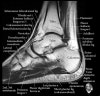

- Coronal section

The coronal oblique T1 sequence follows the tendons of the ankle around the malleolar turns and also evaluates the medial ankle ligaments.

The coronal oblique PD fat suppressed sequence follows the tendons of the ankle around the malleolar turns and is particularly important in evaluation of the Posterior tibialis tendon.

Bone and marrow

Talar dome

Deltoid ligament

Tendons in arch

Plantar fascia

Troubleshoot ligaments